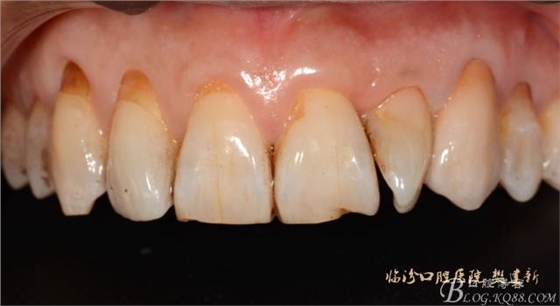

口內(nèi)檢查: 23殘根,位于齦上3MM,根管口探無(wú)反應(yīng),叩(+-),無(wú)松動(dòng),牙周無(wú)紅腫.X片示:23根管無(wú)阻射,根尖骨密度降低.11.12.13頸部楔形缺損,探敏感,牙髓活力正常.全口牙結(jié)石色素(+).

圖123口內(nèi)修復(fù)前情況:殘根位于齦上3MM,牙周無(wú)紅腫.

圖12修復(fù)體代入口內(nèi)正面照